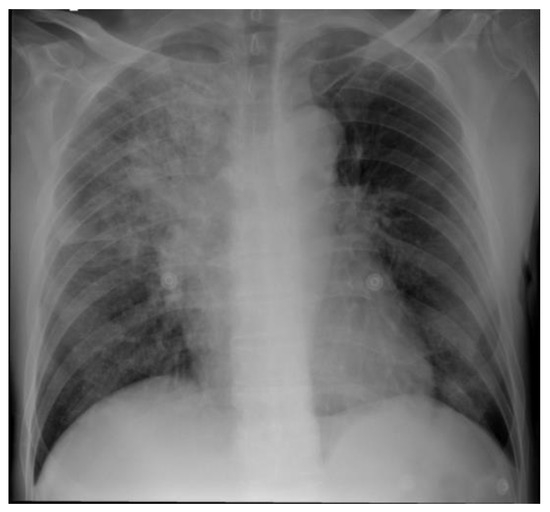

Introduction: Hypertension is occasionally associated with congenital hydronephrosis. Case report: The authors report a four-month-old boy with severe left congenital hydronephrosis and transient hypertension triggered by his first urinary tract infe...